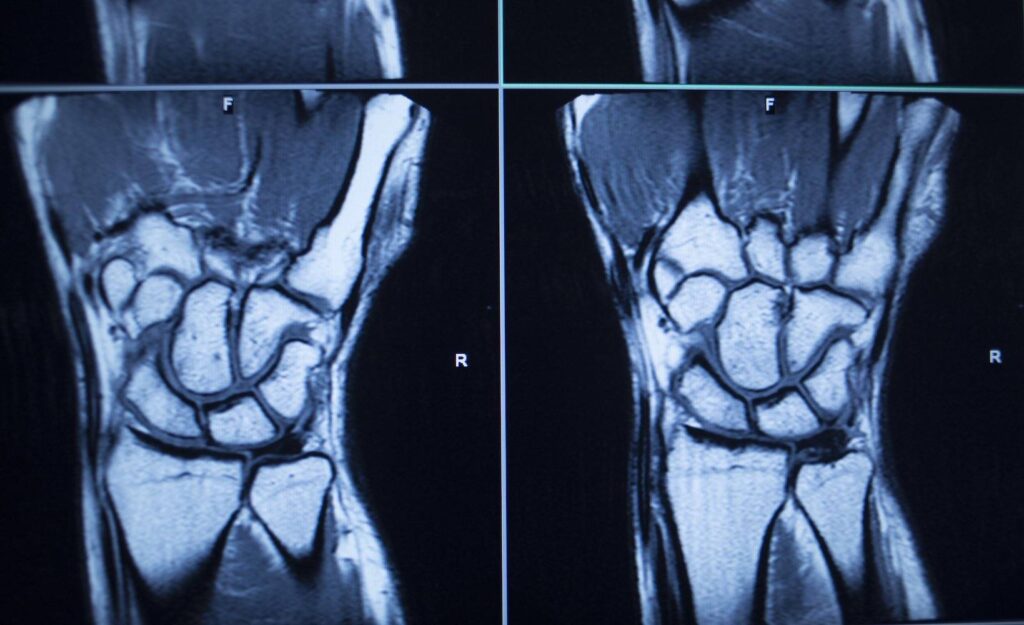

Handgelenksfraktur MRT

Bei einer MRT-Untersuchung des Handgelenks erstellt das MRT-Gerät eine Reihe von Bildern des Gelenks, die aus verschiedenen Winkeln aufgenommen werden, um ein klares Bild des Knochens zu erhalten. Alle oben genannten Erkrankungen können mit Hilfe eines MRT-Scans diagnostiziert werden. Bei einigen Patienten kann die bildgebende Untersuchung jedoch kontraindiziert sein.